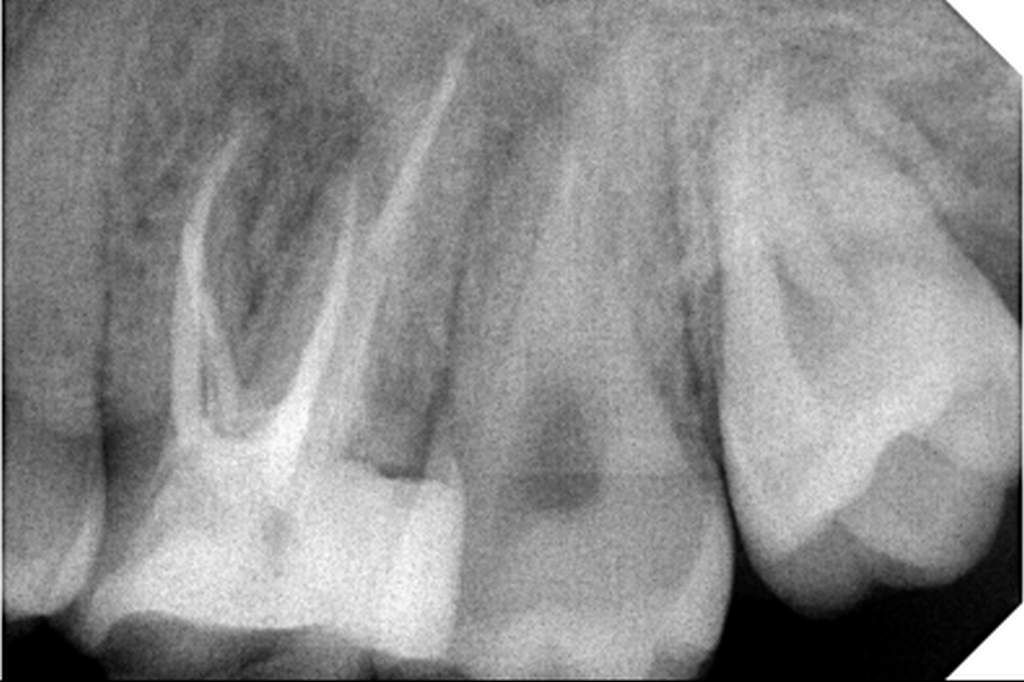

Αρχική εικόνα δοντιού

Εικόνα δοντιού μετά από επανάληψη θεραπείας

Ατελής ενδοδοντική θεραπεία που οδήγησε σε περιακρορριζική καταστροφή.

Η επανάληψη της ενδοδοντικής θεραπείας δεν οδήγησε σε πλήρη επούλωση της βλάβης,

καθώς είναι αναγκαία και η περιοδοντική θεραπεία του δοντιού.